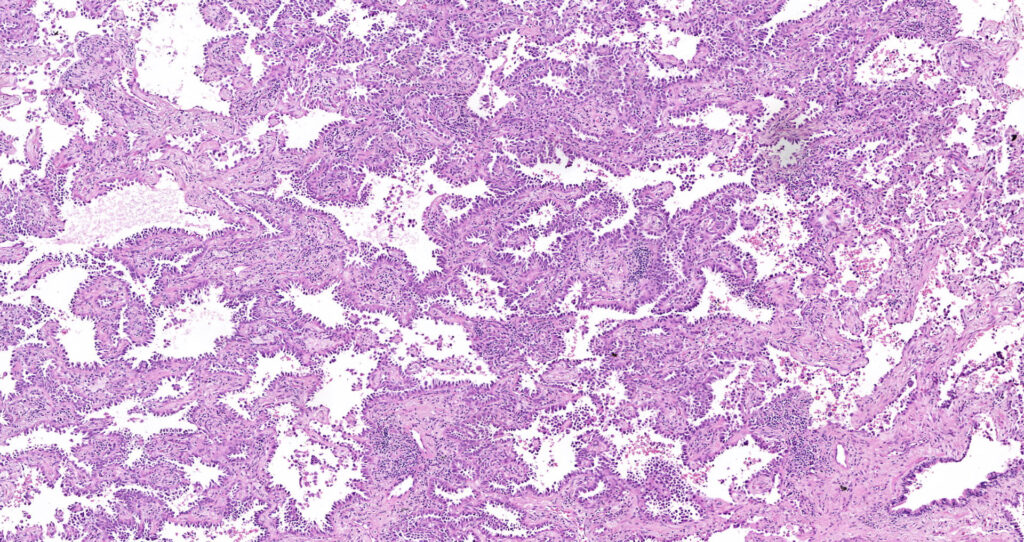

We are happy to announce our new service for our Clients. From the 1st of September, 2020 BioPartners offers you high quality virtual slides (whole slide images) of our banked FFPE samples. Our archive contains more than 1000 scanned images of different types of malignant neoplasms and normal tissues.

Besides, BioPartners offers slide scanning services to medical professionals and organizations at very affordable prices. What you need to do is to send us your glass slides with the completed order form and you will get them back along with the high-resolution and extra-quality virtual slides. Digital slides are either delivered on a DVD (in case of 1-2 glass slides) or an external hard drive. The slide viewing software will be provided as well. Scan type: illumination – bright field, objective magnification – 20x. Approximate size of the digital slide will be between 700MB and 2.5Gb. On your request, your FFPE (formalin fixed, paraffin embedded) or TMA tissue sample can be microtomed and H&E stained.